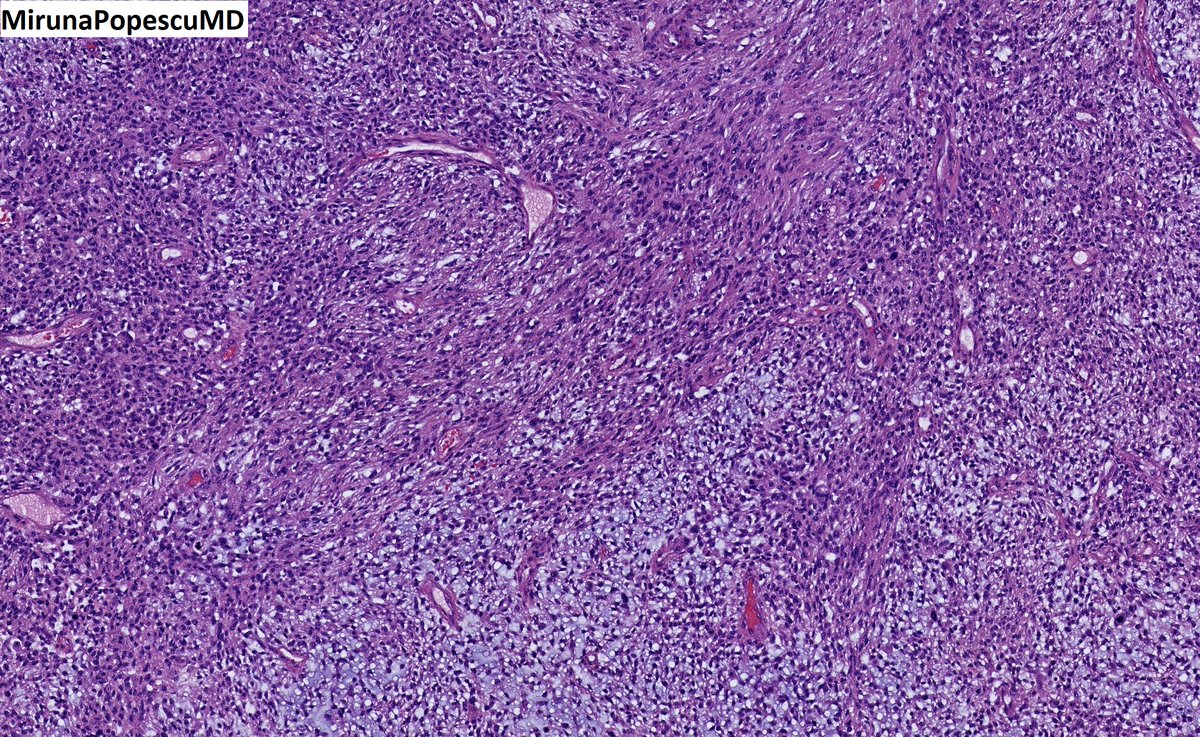

@MirunaPopescu13

❓ Let’s do a quick #BSTPath quiz ❓ 60 y/o F with a retroperitoneal mass 🔪 Follow the 🧵 👇🏽 for the answers & for a short tweetorial (1/11) #PathTwitter #pathoutpic #pathtweetorial